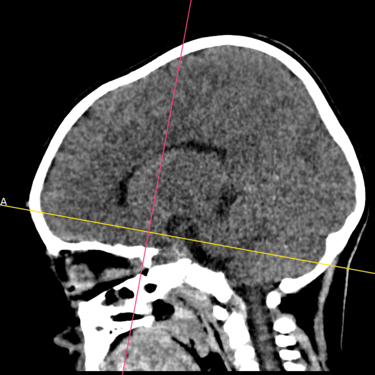

Fractura Craneal | Diagnóstico por Tomografía

La fractura craneal es una lesión que puede producirse tras un traumatismo craneoencefálico, con riesgo de comprometer el cerebro y las estructuras intracraneales. Los síntomas incluyen dolor local, edema, hematomas y, en casos graves, alteración del nivel de conciencia. La tomografía computarizada (TC) es el estudio de elección para su diagnóstico, ya que permite identificar con precisión el trazo de fractura, desplazamientos óseos, hemorragias asociadas y la afectación de senos venosos o base de cráneo. Un diagnóstico temprano mediante TC es esencial para definir la conducta terapéutica y prevenir complicaciones neurológicas potencialmente graves.